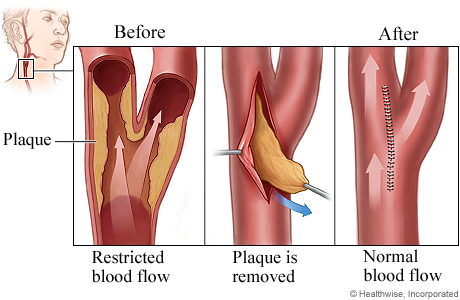

Carotid endarterectomy: To clean or open the carotid artery, a surgeon cuts into the blocked portion, removes the internal lining (and plaque) that’s causing the blockage and repairs the artery with a patch. (See illustration below.)